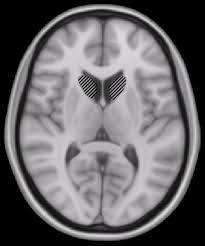

A caractetrística patológica mais marcante é a degeneração do núcleo caudato, uma estrutura que fica no centro do cérebro (veja abaixo).

O núcleo caudato é essa massa que faz pressão sobre a área aberta do cérebro, o ventrículo lateral. Compare com o cérebro de um paciente com DH: